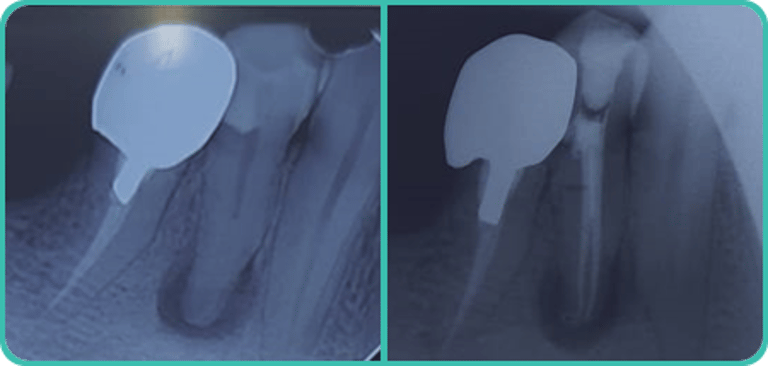

Próteses e implantes dentais:

Intervenções diversas em abordagem única, pensadas para cada caso específico, visando à recuperação da funcionalidade (parcial ou total) dos dentes e à estética do sorriso, sempre buscando os melhores resultados, conforme as escolhas de nossos clientes.